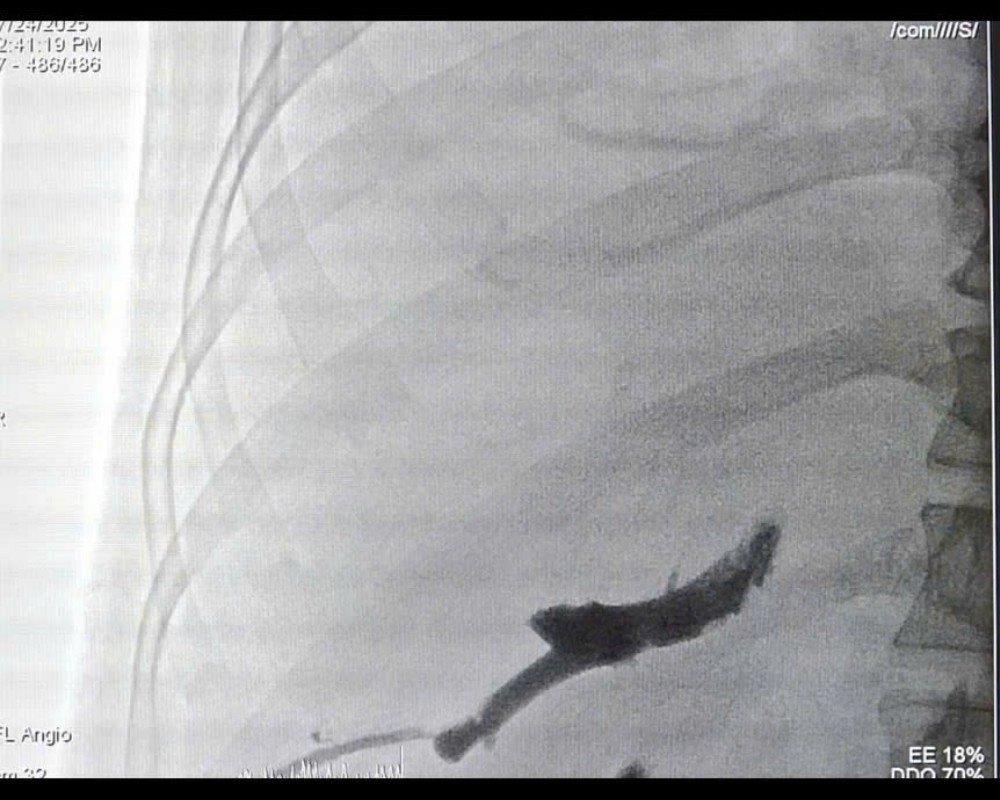

Quá trình can thiệp gây tắc tĩnh mạch cửa bên phải (PVE) - Ảnh BVCC

Trước tình huống này, các ê kíp chuyên môn đã hội chẩn liên khoa và quyết định thực hiện kỹ thuật can thiệp nút mạch gây tắc tĩnh mạch cửa bên phải (PVE). Thủ thuật này giúp chặn dòng máu nuôi phần gan phải có khối u và đồng thời thúc đẩy phần gan lành bên trái phát triển về thể tích. Chỉ sau 4 tuần, thể tích gan trái tăng lên 36,8% tổng thể tích gan, đủ điều kiện tiến hành phẫu thuật.